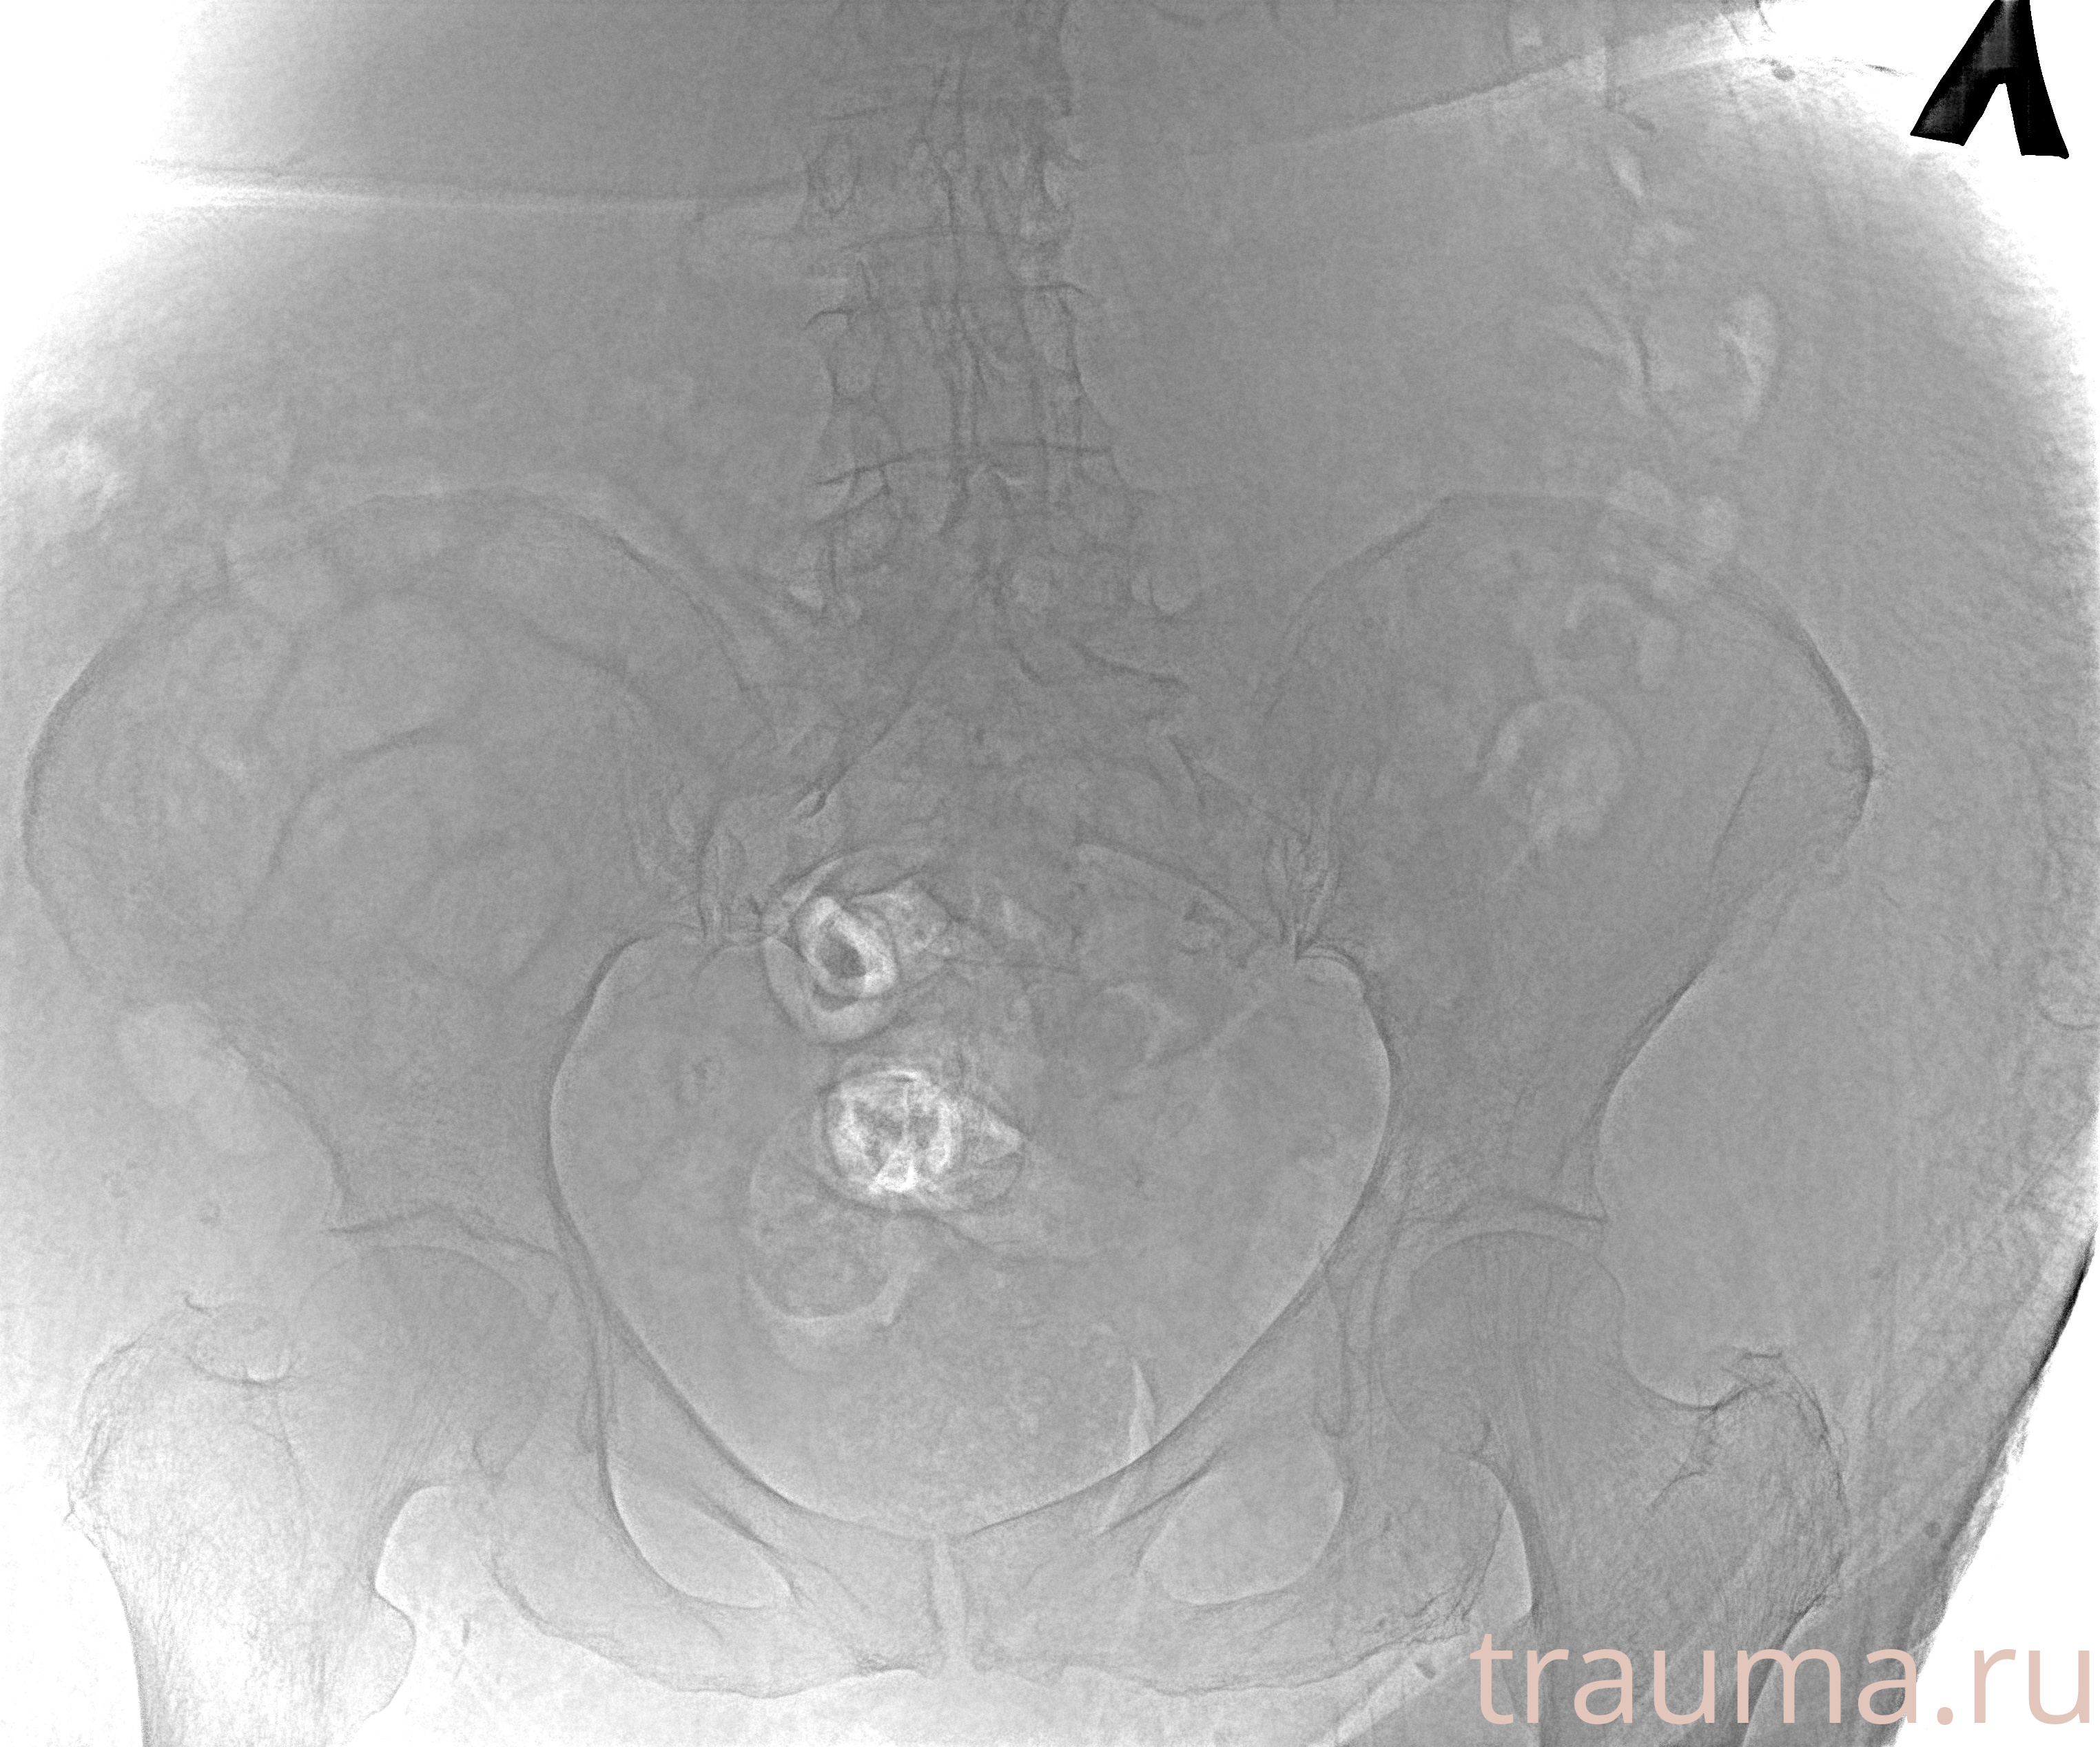

Рентген на дому: по вашему адресу приезжает врач-рентгенолог, травматолог-ортопед с мобильным рентгеновским аппаратом, проводит диагностику травмы или заболевания, делает необходимые рентгенограммы, дает рекомендации по дальнейшему лечению. Получить качественные снимки в домашних условиях возможно благодаря уникальной методике, разработанной МосРентген Центром для института  Склифосовского